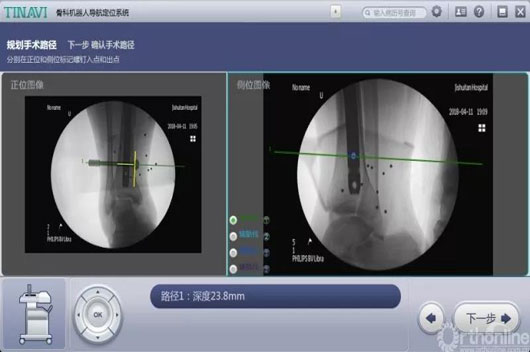

4.jpg

术中妄想远端锁钉位置